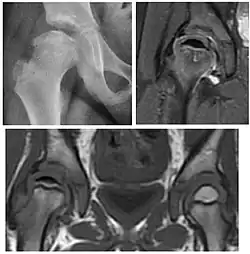

Figure 1.

-

Radiography in normal hip -

X-ray in pincer impingement type of hip dysplasia -

X-ray of cam -

Hip in osteoarthritis -

Septic arthritis

X-ray in pediatrics

Projectional radiography ("X-ray") is the first imaging technique of choice in hip pain, not only in older people with suspected osteoarthritis but also in young people without any such suspicion. In this case plain radiography allows categorization as normal hip or dysplastic hip, or with impingement signs, pincer, cam, or a combination of both.[1]

Plain radiography allows us to categorize the hip as normal or dysplastic or with impingement signs (pincer, cam, or a combination of both). Besides these, pathologic processes like osteoarthritis, inflammatory diseases, infection, or tumors can also be identified (Figure 1).[1]